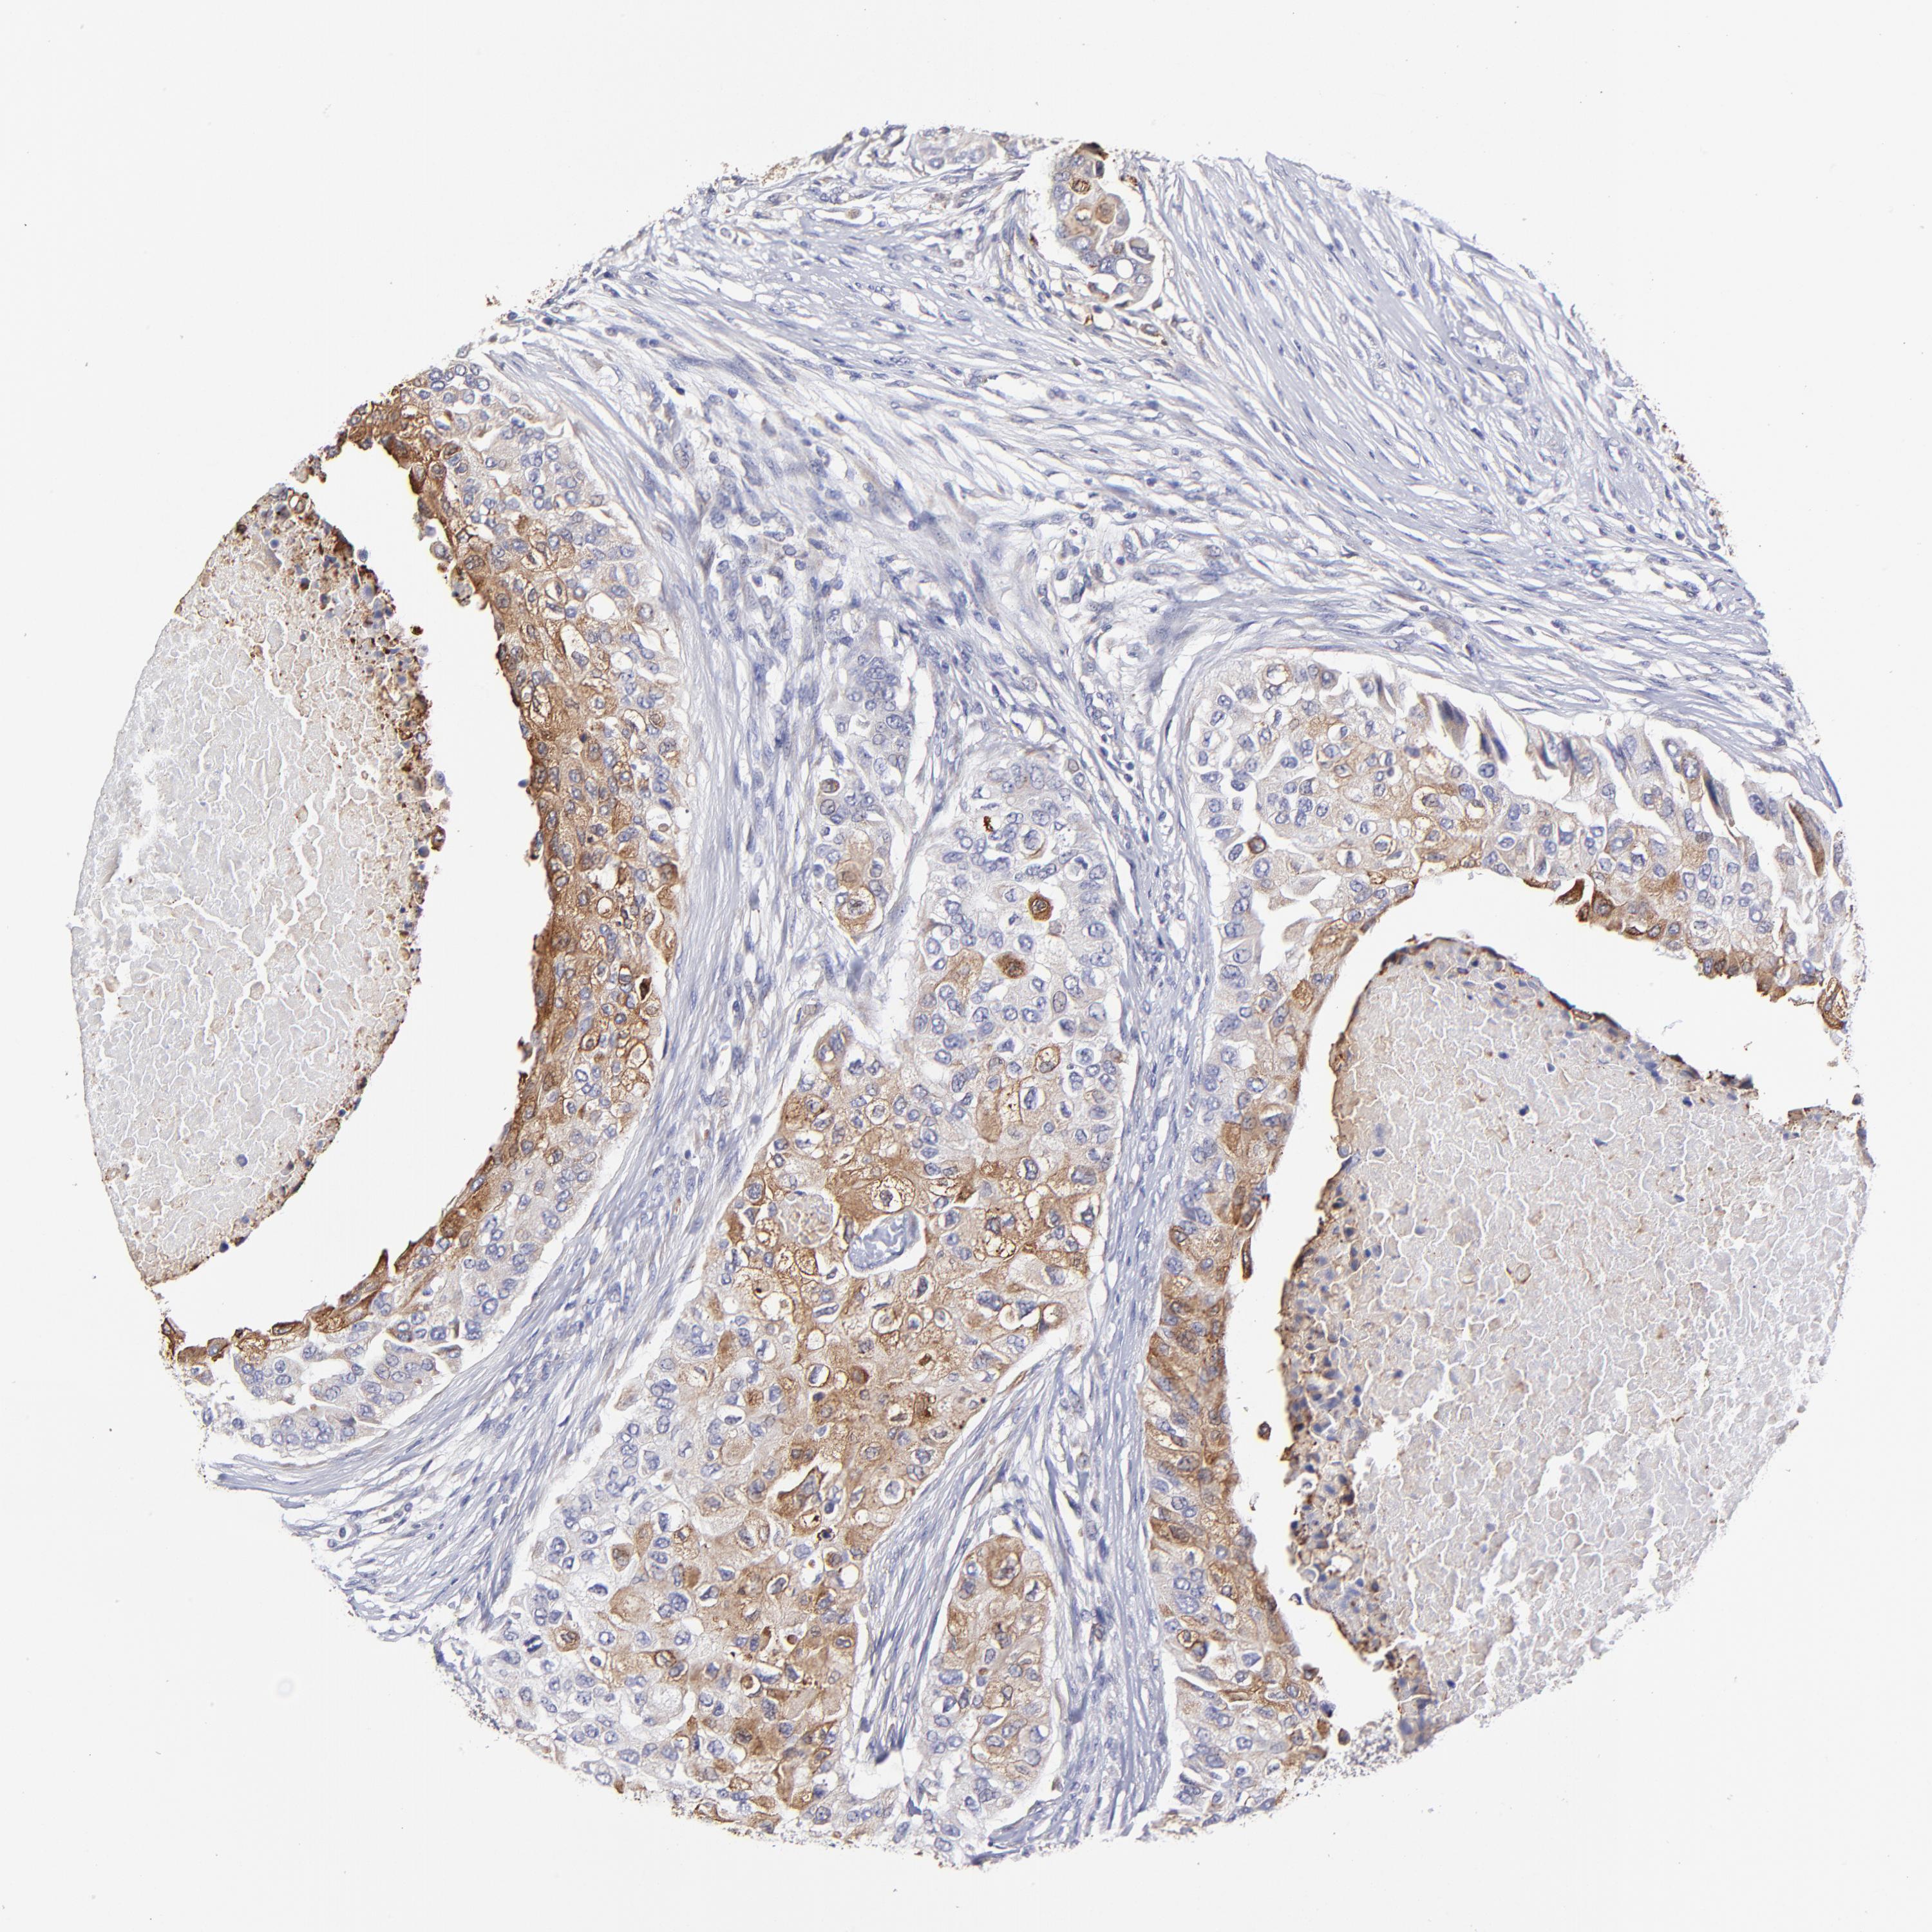

CANCER BREAST CANCER Show tissue menu

BRCA TCGA BRCA VALIDATION PROTEIN EXPRESSION